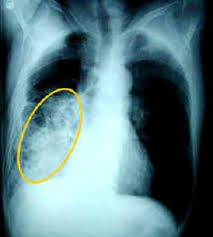

Η πνευμονία της κοινότητας παραμένει μία από τις πιο συχνές αιτίες θανάτου στις Ηνωμένες Πολιτείες της Αμερικής καθώς και σε όλο τον κόσμο. Αν και η διάγνωση της πνευμονίας γίνεται άμεσσα στις περισσότερες περιπτώσεις, υποκείμενα καρδιολογικά, αναπνευστικά προβλήματα υγείας όπως και η άτυπη εμφάνιση (χωρίς τυπική κλινική εικόνα) σε ηλικιωμένους ασθενείς μπορεί να καθυστερήσουν την αναγνώρισή της. Η τριάδα των συμπτωμάτων που δείχνουν ότι υπάρχει λοίμωξη (πυρετός ή ρίγος και αύξηση των λευκών αιμοσφαιρίων στην εξέταση αίματος), σημεία ή συμπτώματα ότι η λοίμωξη αυτή εντοπίζεται στους πνεύμονες (βήχας, παραγωγή πτυέλων, δυσκολία στην αναπνοή, πόνος στο θώρακα ή παθολογικά ευρήματα στην εξέταση από τον γιατρό) και η διαπίστωση ενός νέου διηθήματος στην ακτινογραφία θώρακος με ακρίβεια αναγνωρίζει έναν ασθενή με πνευμονία της κοινότητας. Οι ηλικιωμένοι ασθενείς μπορεί να μην έχουν την παραπάνω τυπική εικόνα ενώ η σύγχυση μπορεί να αποτελεί το μόνο σύμπτωμα τους με αποτέλεσμα να καθυστερεί η διάγνωση. Επίσης τα ευρήματα στην ακτινογραφία μπορεί να είναι ήπια: έτσι ένας μεμονωμένος ακτινολόγος μπορεί να μην αναγνωρίσει διηθήματα στην ακτινογραφία σε ποσοστό έως και 15% και 2 ακτινολόγοι μπορεί για την ίδια ακτινογραφία να διαφωνήσουν σε ποσοστό 10%.

ακτινογραφία θώρακος (face+profil) θα δείξει πνευμονικά διηθήματα με ή χωρίς συλλογή πλευριτικού υγρού.